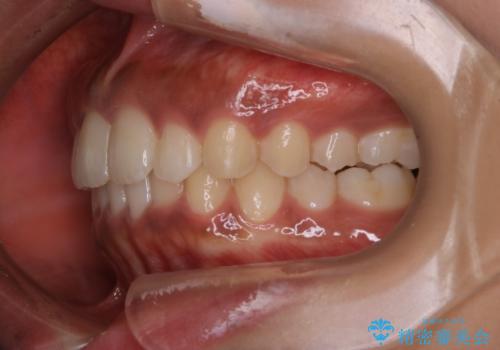

インビザライン矯正 歯を抜かずに出っ歯を改善!

- 出っ歯と前歯の隙間が空いていることを気にされて来院されました。

また、自然な感じで口元を下げていとのことでした。

奥歯のかみ合わせが問題なかったため、上顎の前歯の隙間を閉じるとともに、上顎の歯の側面を削ることをメインにして、出っ歯を改善する治療計画としました。

上顎の歯の傾きを変えるうえで、下顎の歯とのバランスのことも考え、下顎の歯の側面も削ることを加えています。

また、今回は口元を変えたい中に、劇的な変化は避けたいとのことだったので、抜歯をしない計画としています。

抜歯をしない場合、口元の変化は感じにくいですが、前歯の傾きが変わることで、口の閉じやすさは感じていただけたとのことです。

症例にもよりますが、本症例は奥歯のかみ合わせに問題がなかったので歯の側面を削ることメインに、前歯の傾きを改善することができました。

抜歯を行う場合や抜歯をしなくても奥歯の位置をずらす場合は、治療期間が長期化することが多いですが、今回は歯を削ることで改善できたため、短期間で治療を完了することができました。